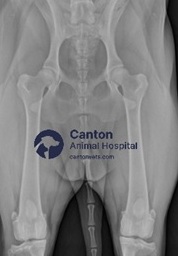

Diagnosing Hip Dysplasia in Dogs

A veterinarian will perform several tests to confirm hip dysplasia, including:

Physical Examination – Checking for pain, stiffness, and joint instability. Hip Manipulation Tests – Techniques like the Ortolani test to detect looseness in the hip joint. X-rays (Radiographs) – The gold standard for confirming hip dysplasia and assessing joint damage. CT or MRI Scans – Used in severe cases to evaluate cartilage and soft tissue damage.

Early diagnosis allows for better treatment options and long-term management.